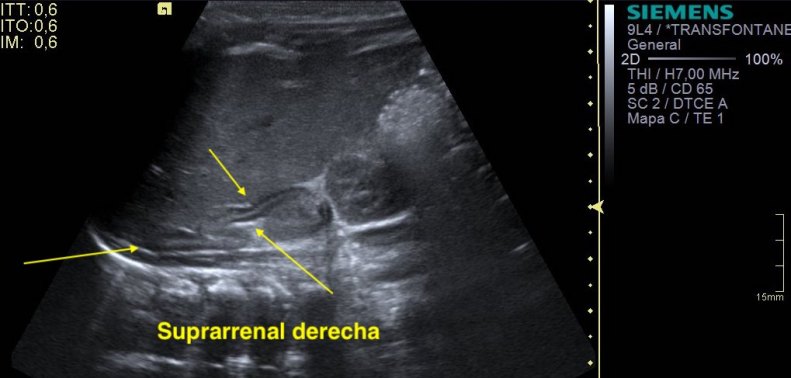

La suprarrenal normal es así:

Son estructuras serpenteantes, en forma de V hipoecogénicas en su parte externa e hiperecogénica en el interior de las mismas, y se encuentran encima del riñón, entre la vena cava y el polo superior del derecho, si estás estudiando este lado derecho…

Las línea amarillas te marcan el recorrido es esta ecoestructura que te cuento cuando se vé normal. Localización y aspecto habituales dentro de la normalidad.